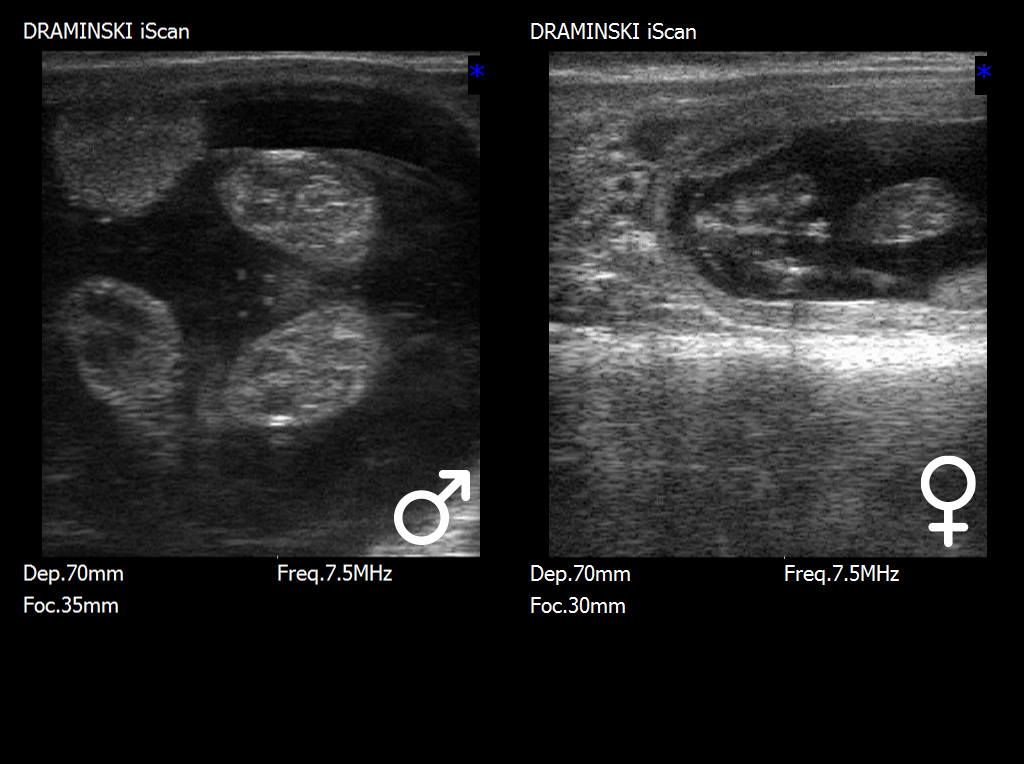

The optimal period for fetal sex determination is between days 55 and 70 of pregnancy.

At this stage, the key diagnostic structure is the genital tubercle (tuberculum genitale), which undergoes characteristic displacement depending on the fetus’s sex. In male fetuses, the genital tubercle shifts toward the umbilicus and the future penis, while in female fetuses, it is located closer to the tail, in the region of the future vulva. Correct interpretation of the tubercle’s position requires not only high-quality ultrasound imaging but also appropriate experience, as small variations in fetal positioning can influence the assessment.

In the later stages of pregnancy, after approximately days 70–80, identification of more developed external genital organs becomes possible, such as the scrotum in male fetuses or vulvar structures in female fetuses. Although sexual characteristics are more apparent at this stage, the examination becomes more challenging due to the increasing size of the fetus, its deeper position within the uterine cavity, and the limited maneuverability of the ultrasound probe.